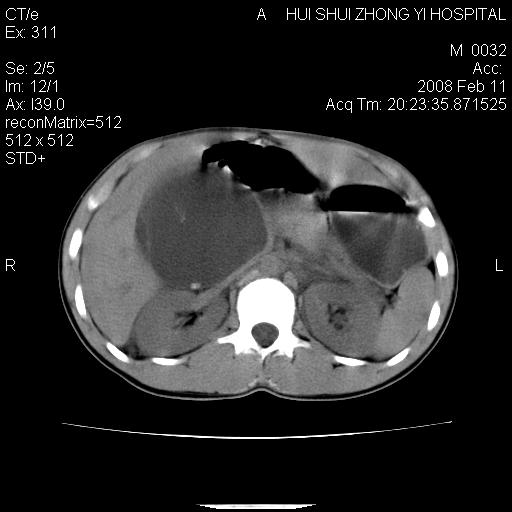

8年前曾在贵洲省人民医院b超诊断为肝内胆管结石。现腹痛剧烈,现发烧、头痛、恶心呕吐县医院b超示胆囊肿大大小159*46mm,囊内见6*5mm强回声光团,胆各总管内径56mm。提示:胆囊结石、急性胆囊炎、胆总管重度扩张。

胆囊结石.急性胆囊炎.重度胆管扩张.右侧胸腔少量积液,建议ct增强

考虑先天性胆管囊肿;胆囊增大并结石。右侧胸腔少量积液,建议ct增强。

caroli囊肿并囊内结石。胆囊增大并胆结石。典型!

先天性胆管囊肿,胆囊结石、胆囊增大,右侧少量胸腔积液。